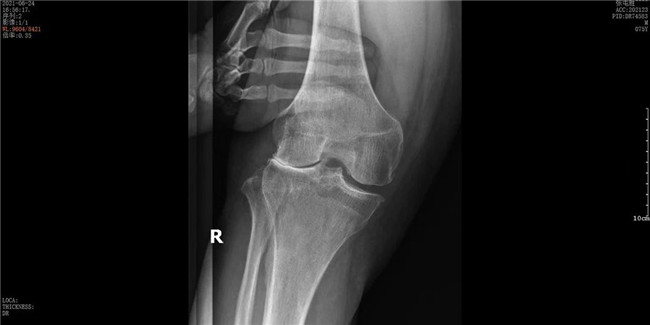

▲右膝關節(jié)外側(cè)間室磨損▲

接診后羅軍主任詳細檢查病人,發(fā)現(xiàn)病人疼痛癥狀主要集中在膝關節(jié)外側(cè)間室,右下肢有明顯外翻畸形。這些癥狀都是單髁置換的適應癥。雙下肢全長攝片和右膝內(nèi)翻、外翻位攝片顯示,膝關節(jié)外側(cè)間隙消失,膝外翻畸形,果不其然印證了上述臨床表現(xiàn)。收治入院后,羅主任團隊決定為患者實施微創(chuàng)膝關節(jié)外側(cè)單髁置換術(shù),盡全力為張大爺解除病痛的折磨。